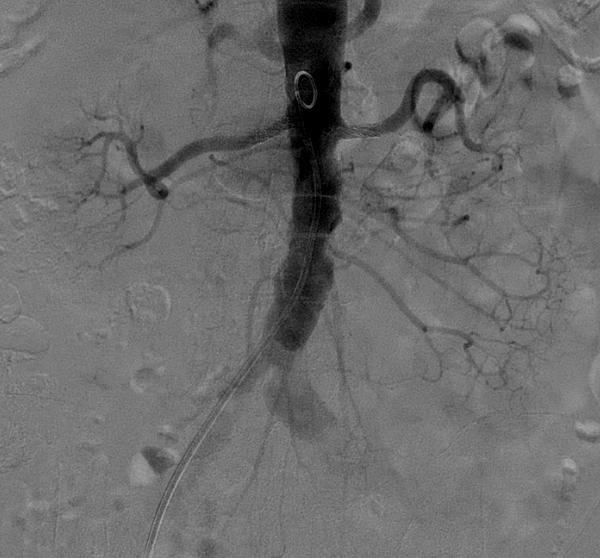

局麻后穿刺右股总动脉并置入7F血管鞘。腹主动脉造影示:腹主动脉管腔不光滑,左侧髂总动脉管腔增粗,双侧肾动脉管腔重度狭窄,右侧可见副肾动脉,左侧副肾动脉显示不清。

全身肝素化,7F RDC配合4F Sim1导管选入右肾动脉,(4mm-20mm)Aviator Plus球囊预扩,植入(6mm-18mm)Palmaz Blue支架。

7F RDC配合4F Sim1导管选入左肾动脉,(4mm-20mm)Aviator Plus球囊尝试送入左肾动脉困难,更换(2mm-15mm)Gateway球囊后成功送入左肾动脉并完成预扩,植入(5mm-18mm)Palmaz Blue支架。

复查造影:支架位置及形态满意,未见明显残余狭窄,双侧肾动脉及分支血流通畅。